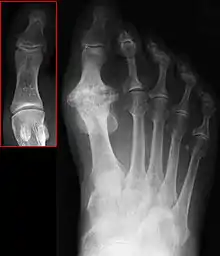

Hallux rigidus or stiff big toe is degenerative arthritis and stiffness due to bone spurs that affects the metatarsophalangeal joints (MTP) at the base of the hallux (big toe).

| Hallux not labeled but visible at upper left. | |

In 1988, Hattrup and Johnson described the following radiographic classification system:

- Grade I – mild changes with maintained joint space and minimal spurring.

- Grade II – moderate changes with narrowing of joint space, bony proliferation on the metatarsophalangeal head and phalanx and subchondral sclerosis or cyst.

- Grade III – severe changes with significant joint space narrowing, extensive bony proliferation and loose bodies or a dorsal ossicle.[3]